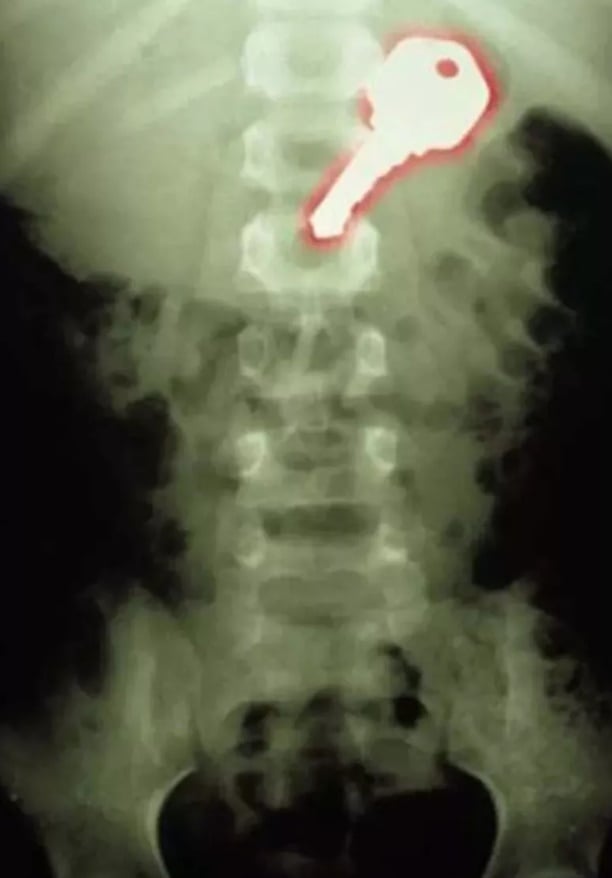

Anahtar yutmuş, 7 yaşındaki bir çocuğa ait renklendirilmiş röntgen...